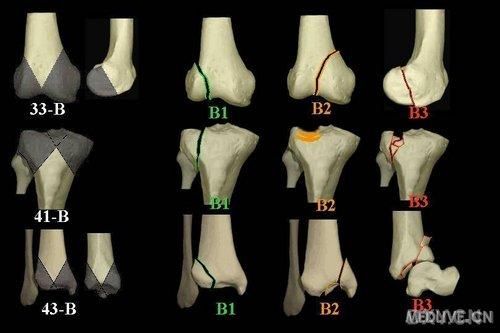

医学教材把骨折分成上百种亚型,但日常最常被问到的只有以下六大类:

- **横行骨折**:骨折线与骨干垂直,像被刀切过,常见于直接暴力。

- **斜行骨折**:骨折线呈斜角,多因扭转暴力导致。

- **螺旋骨折**:骨折线绕骨干旋转,**滑雪、摔跤**是高发场景。

- **粉碎性骨折**:骨头碎成三块以上,**车祸、高处坠落**最常见。

- **压缩骨折**:椎体被压扁,老年人骨质疏松后轻微跌倒就可能发生。

- **青枝骨折**:儿童骨骼弹性大,折而不断,像嫩枝被折弯。

在骨折图片大全里,每一类都配有标准X光片与手绘示意图,方便对照。